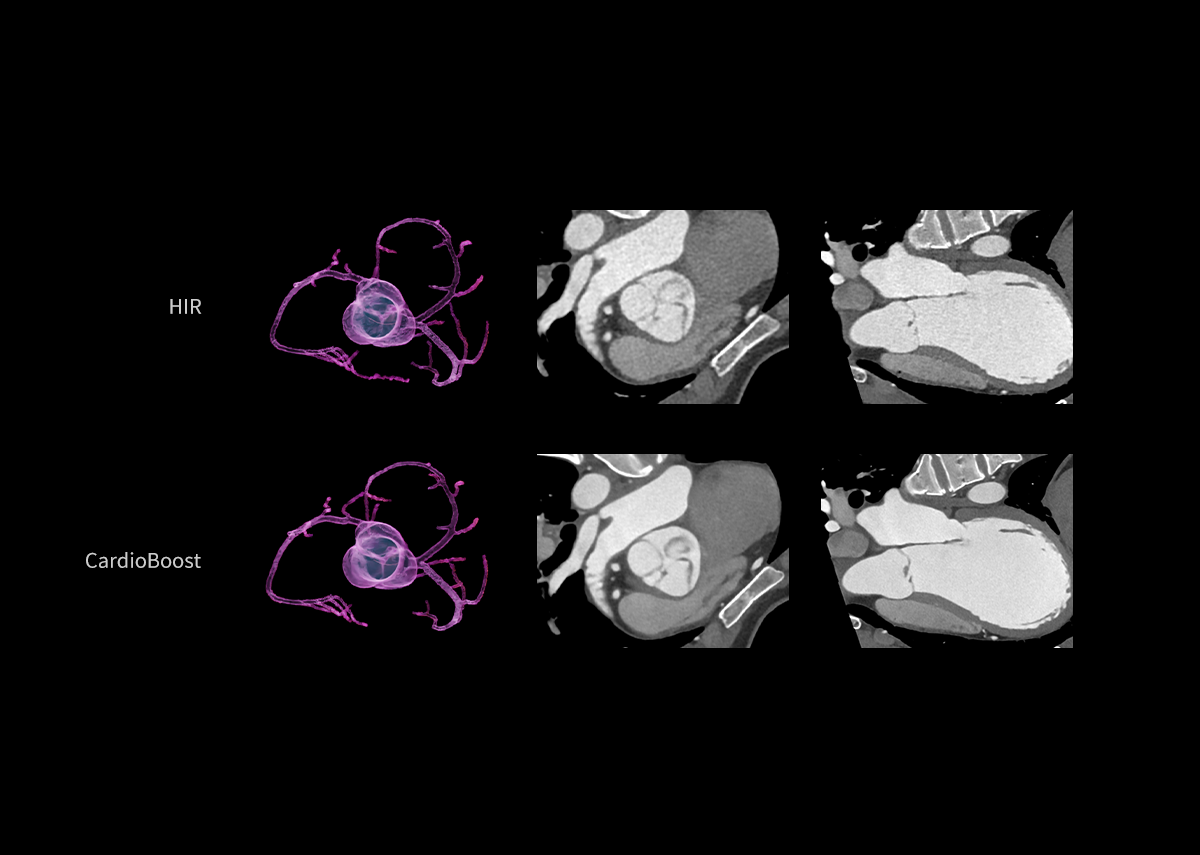

AIIR* – AI Iterative Reconstruction

Throughout the iterative loop of forward and backward projection between the raw data domain and the image domain, AIIR consistently takes into account the accurate modeling of optics, noise, anatomy, and physics statistics. Additionally, AIIR integrates deep learning-based de-noising technology, supplanting the conventional regularization role of MBIR in the optimization reconstruction process.

In brief, AIIR utilizes deep learning-based AI technology to attain robust noise reduction and natural image texture, while incorporating MBIR technology to achieve precise anatomical structure representation and artifact suppression. This technique surpasses the limitations of using either MBIR or deep learning reconstruction (DLR) independently.